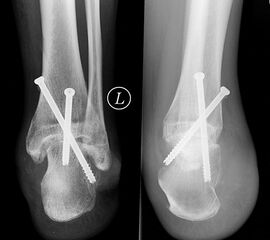

Weite Resektion

Bei der operativen Therapie maligner Neoplasien ist im Rahmen eines kurativen Therapie­ansatzes die weite Resektion zwingend erforderlich. Dabei richtet sich das jeweilige operative Vorgehen mit der nachfolgenden Rekonstruktion nach der Lokalisation des Tumors. Bei Läsionen im Bereich der distalen Tibia ist eine Segmentresektion des Knochens mit möglicher Überbrückung des Defekts durch Verwendung eines Tibia-Verschiebespans oder Fibula-Autografts und gleichzeitige Arthrodese im Bereich des oberen Sprunggelenks möglich. Aufgrund der hohen Belastung in diesem Extremitätenabschnitt ist eine Doppelung der Fibula und Anlagerung zusätzlicher Beckenkammspongiosa zu diskutieren (Burgkart, 2003). Bei Neoplasien im Bereich der distalen Fibula kann mit segmentaler Resektion des betroffenen Knochenabschnitts inklusive lateralem Malleolus und Durchführung einer tibio-talaren Arthrodese mit geringgradiger Extremitätenverkürzung meist ein funktionell gutes Ergebnis erzielt werden. Ist der Knochentumor im Bereich der posterioren Talusanteile lokalisiert so kann nach Osteotomie im Bereich des Talushalses unter Verkürzung der Extremität eine tibiocalcaneare Arthrodese mit Einbeziehung des restlichen Talus im Sinne einer Blair-Arthrodese durchgeführt werden 28. Bei Tumoren im Bereich des Calcaneus, die eine weitere Resektion notwendig machen, ist entweder eine Syme-Amputation oder die isolierte Resektion des Calcaneus mit Versorgung des entstandenen Defekts durch einen myo-cutanen Lappen und Verwendung spezieller Schuhe möglich (Burgkart, 2003). Ausgeprägte Befunden, die über die Höhe des oberen Sprunggelenks hinausreichen, erfordern selten eine distale Unterschenkelamputation (Abb. 10a-e). Die früheren Amputationsschemata, die von Amputationen in der distalen Hälfte des Unterschenkels abgeraten haben, besitzen heute keine Gültigkeit mehr 29. Dem Erhalt der Länge ist nach Beachtung einer entsprechenden Radikalität der Tumorresektion höchste Priorität zu bemessen. Bei Tumorlokalisation im Bereich des Mittelfußes können nach vollständiger Entfernung des jeweiligen Knochens Rekonstruktionen unter Verwendung autologer oder allogener struktureller Transplantate ("strut grafts") zu funktionell guten Mittelfußarthro­desen führen (Abb. 11) (Burgkart, 2003). Mit Ausnahme der großen Zehe können Amputationen der Zehen meist gut kompensiert werden. Amputationen in Höhe der Grund- und Mittelglieder der Kleinzehen sind wegen der Imbalance der Muskulatur mit sekundären Fehlstellungen zu vermeiden 29.